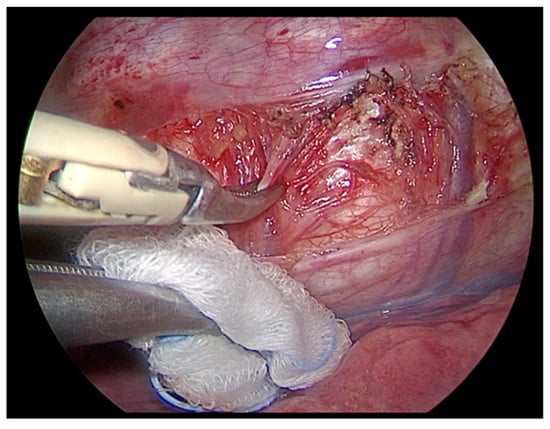

2.2.2. Surgical Technique

- The risk of bleeding is possible especially near the Azygos vein. The vascular dissection must be delicate and precise, using a bipolar forceps or a thin instrument combined with a bipolar coagulation device. The parietal pleura must be incised carefully along the marginal spine and a good exposure of the veins must be achieved. Small branches of the paravertebral veins need accurate hemostasis.